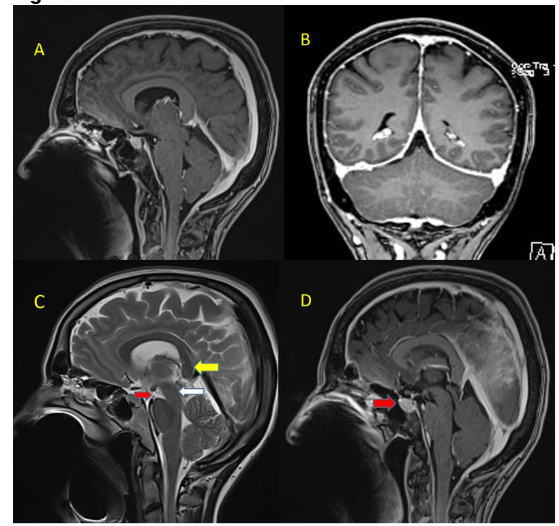

Figure 3A and 3B- contrast enhanced T1 weighted sagittal and axial MRI of the spine showing smooth dural enhancement

Figure 3A and 3B- contrast enhanced T1 weighted sagittal and axial MRI of the spine showing smooth